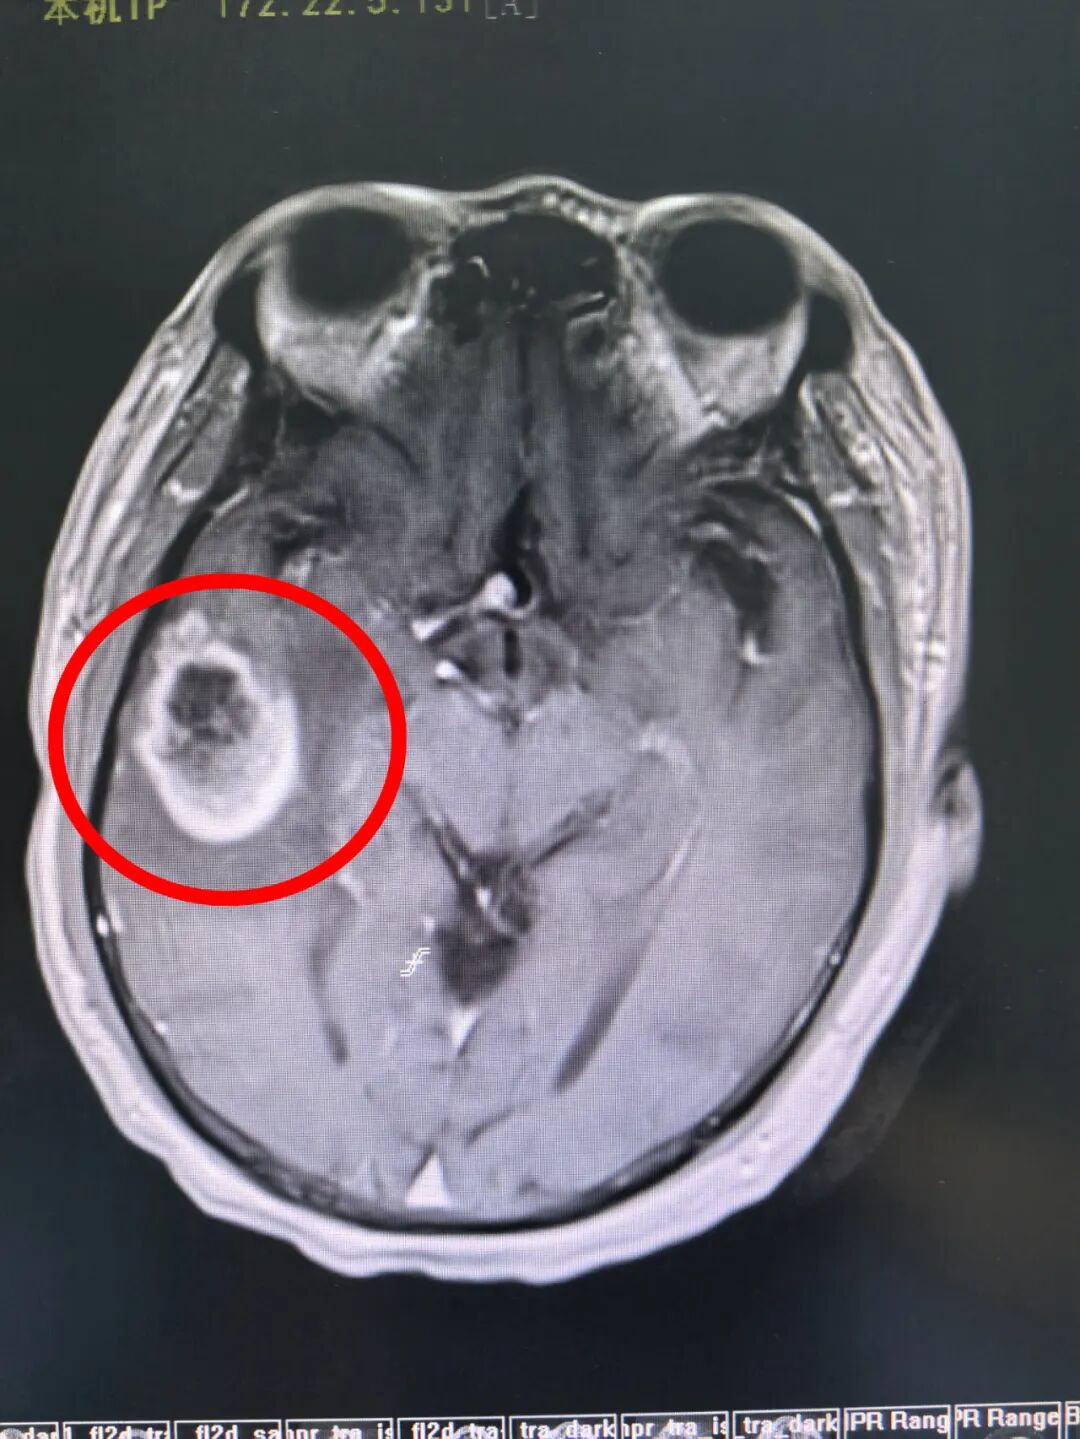

患者陈先生因抽搐伴突然意识丧失被紧急送往医院。初步检查,医生发现他右侧颞叶长有一个肿瘤(考虑为胶质瘤),随后陈先生便入住神经外科。

然而,进一步详细检查有了惊人发现:患者大脑前交通位置还存在一个致命的动脉瘤!先切除肿瘤还是先处理动脉瘤?这一难题让医生犯了难。

双瘤并存

若先处理动脉瘤,由于该动脉瘤是宽颈,介入栓塞需支架辅助才能治愈。一旦放置支架,患者需口服抗凝药物半年,这半年内无法进行开颅手术。而这半年间,肿瘤会持续生长,不仅会压迫脑组织,引发更多神经功能障碍,还可能致使颅内压急剧升高,直接危及生命。要是仅先切除肿瘤,动脉瘤随时有破裂风险,一旦破裂,致死致残率极高! 这确实是个艰难的抉择。